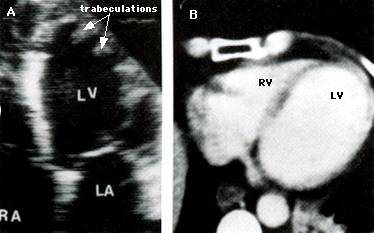

Ecocardiografia

Confirma diagnosticul de CMH, cuantifica elementele morfologice - distributia hipertrofiei, functionale - hipercontractilitatea VS si hemodinamice - gradientul intraventricular.

Caracterele ecocardiografice sunt :

Maron si colaboratorii descriu 4 tipuri de hipertrofie in CMH :

tipul I - hipertrofie localizata in portiunea anterioara a SIV

tipul II - hipertrofia intereseaza tot SIV, peretele liber este normal

tipul III - hipertrofia cuprinde SIV si peretele anterior, peretele inferior este normal

tipul IV - hipertrofie localizata in alte parti ale peretelui liber, nu cuprinde portiunea anterioara a SIV dar poate afecta alte zone (peretele anterior, peretele lateral, portiunea posterioara a SIV, peretele posterior sau apexul VS in forma apicala).

Cea mai frecventa este CMH tip I (in 90 % din cazuri), dar se poate intalni si hipertrofia simetrica de perete.

Examenul Doppler evidentiaza prezenta gradientului, a insuficientei mitrale si anomaliile functiei diastolice.